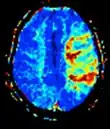

| Ponderado em difusão (DWI) | Convencional | DWI | Medição do movimento browniano das moléculas de água. | Sinal alto dentro de minutos após um infarto cerebral.[74] | ![]() |

| Coeficiente de difusão aparente | ADC | Ponderamento reduzido em T2, usando várias imagens convencionais de DWI com diferentes ponderações de DWI, sendo a mudança correspondente à difusão. | Sinal baixo minutos após um infarto cerebral.[75] | ![]() | |